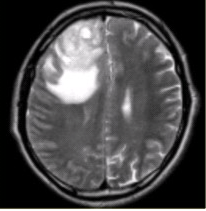

患者女,68岁。头痛、恶心2周,加重2d。头CT显示如下图。

可能的诊断是(提示头颅CT增强及CT灌注成像(脑血流量及表面渗透值明显升高)显示如下图。)()

A.病变与脑实质边界不清,跨越大脑镰提示病变位于轴内

B.病变密度较高,提示内部伴发出血

C.病变邻近颅骨可见骨质肥厚,支持病变位于轴外

D.病变形态不规则,周围水肿明显,支持病变位于轴外

E.为进一步明确诊断,需增强检查

F.CT平扫可以评价病变与硬脑膜的关系

CT、MR支持病变位于轴外的征象是()

A.病变边界清晰,形态不规则,呈分叶状

B.病变邻近的蛛网膜下腔增宽

C.病变呈等T1等T2信号影

D.大脑镰可见明显强化,CBV及PS明显升高

E.病变周围水肿明显

F.病变占位效应明显

可能的诊断为(提示进一步MRI检查显示如下图。)()

A.脑膜瘤